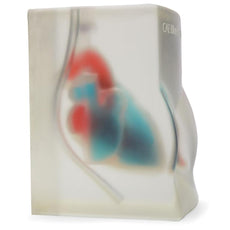

Replacement tissue insert for the Thoracentesis and Thoracostomy Ultrasound Training Model (BPTT1000-1).Choose from three options:

- Tissue Insert

- Anterior Portal Insert

- Lateral Portal Insert